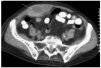

Mujer de 80 años, con antecedentes de hipercolesterolemia, que ingresó en la unidad de cuidados intensivos por presentar dolor epigástrico irradiado al cuello y acompañado de signos vegetativos. En el electrocardiograma se apreció elevación del segmento ST en la cara anterolateral compatible con infarto agudo de miocardio. Se realizó tratamiento fibrinolítico con TNK, heparina sódica, nitroglicerina y ácido acetilsalicílico. A las 60 h se suspendió la heparina sódica y se inició tratamiento con enoxaparina. A la semana de evolución se inició un dolor abdominal en la fosa ilíaca derecha, presentando en la exploración dolor a la palpación superficial y signo de Blumberg positivo. Se realizó una TAC abdominal donde se apreció hematoma con nivel, localizado en los rectos anteriores (fig. 1). La paciente fue tratada de forma conservadora con analgesia, suspensión de la enoxaparina y transfusión de concentrado de hematíes. La evolución posterior fue satisfactoria.

Figura 1